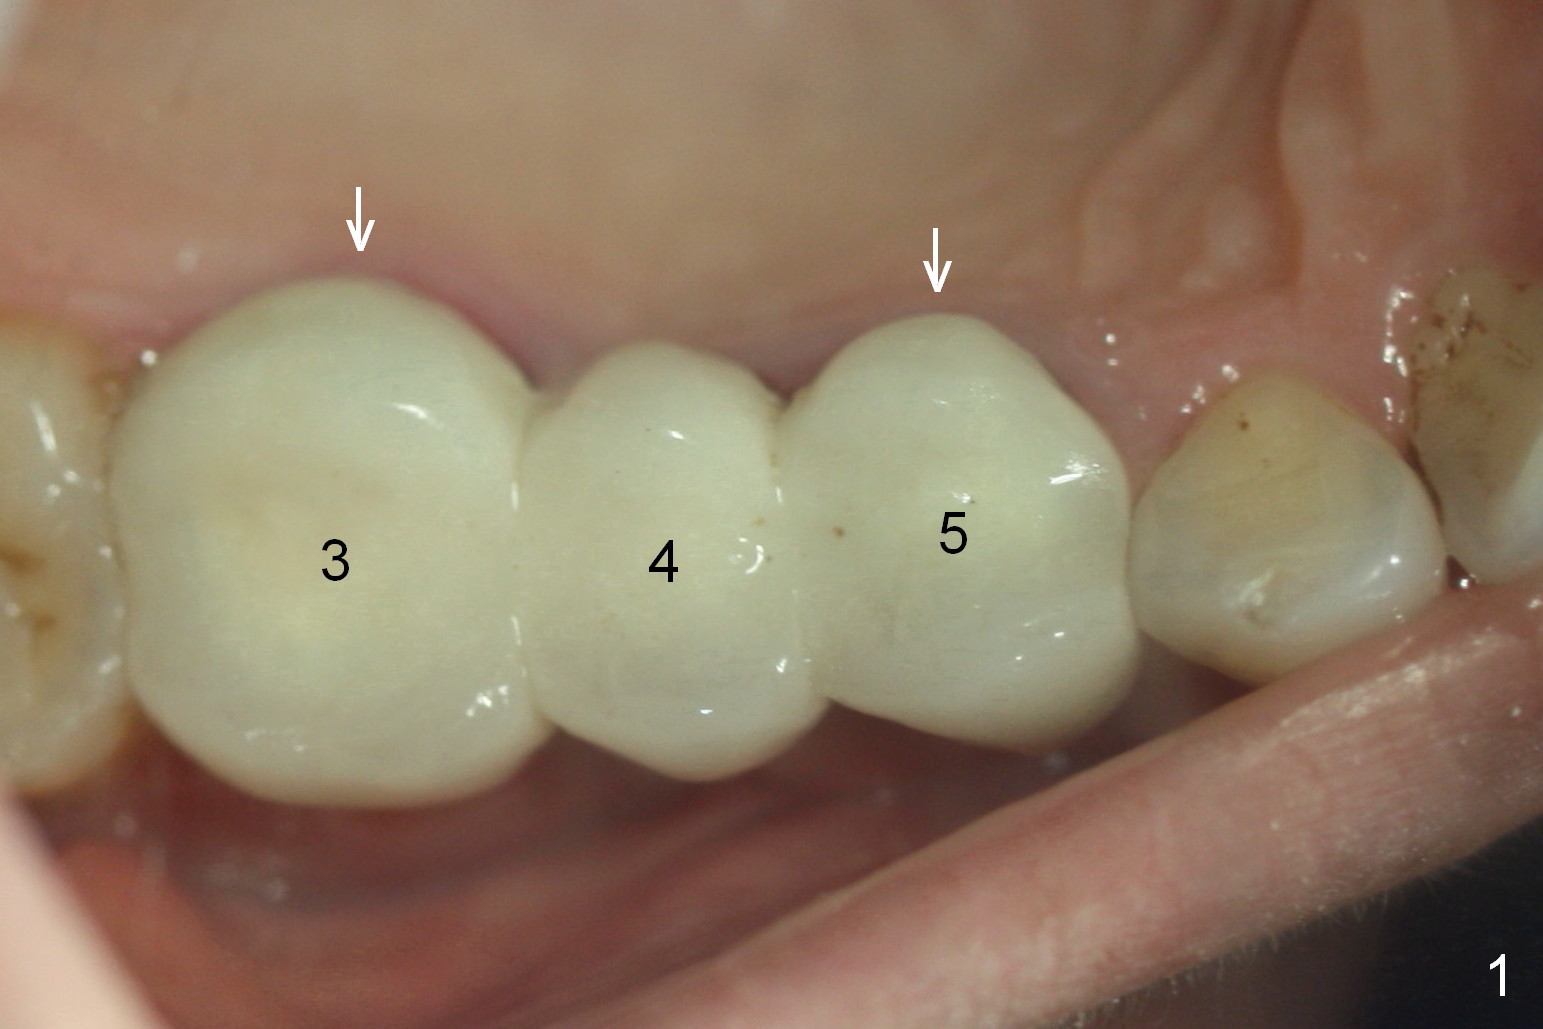

Ms. Li, a 34-year-old lady, had the upper right fixed partial denture made by an unlicensed dentist in California 10 years ago (Fig.1: #3-5). The gingival margin palatal to the retainers is erythematous (Fig.1 arrows). The patient's chief complaint is gum bleeding. The retainer at #3 is over-contoured buccopalatally (Fig.1, as compared to #14 in Fig.2), while the one at #5 is over-contoured buccopalatally and mesiodistally (compare to #12 in Fig.2). Panoramic X-ray (Fig.3), bitewing (Fig.4) and periapical film (Fig.5) all confirm that the bridge is over-contoured and that the retainers #3 and 5 have open margin (Fig.4 arrowheads). To improve oral hygiene and save the abutment teeth #3 and 5, it is in the patient's best interest to remove the bridge, place an implant at #4 and fabricate single-unit crowns at #3 and 5. Three to four months later, pyogenic granuloma develops between #4 and 5 (Fig.6 *) with generalized gingival erythema apically. The pontic at #4 and the retainer at #5 are to be removed first. An implant will be placed at #4 (Fig.7) with conjoined provisional at #4 and 5. The initial depth of osteotomy is 13 mm with Sinus Master Kit.